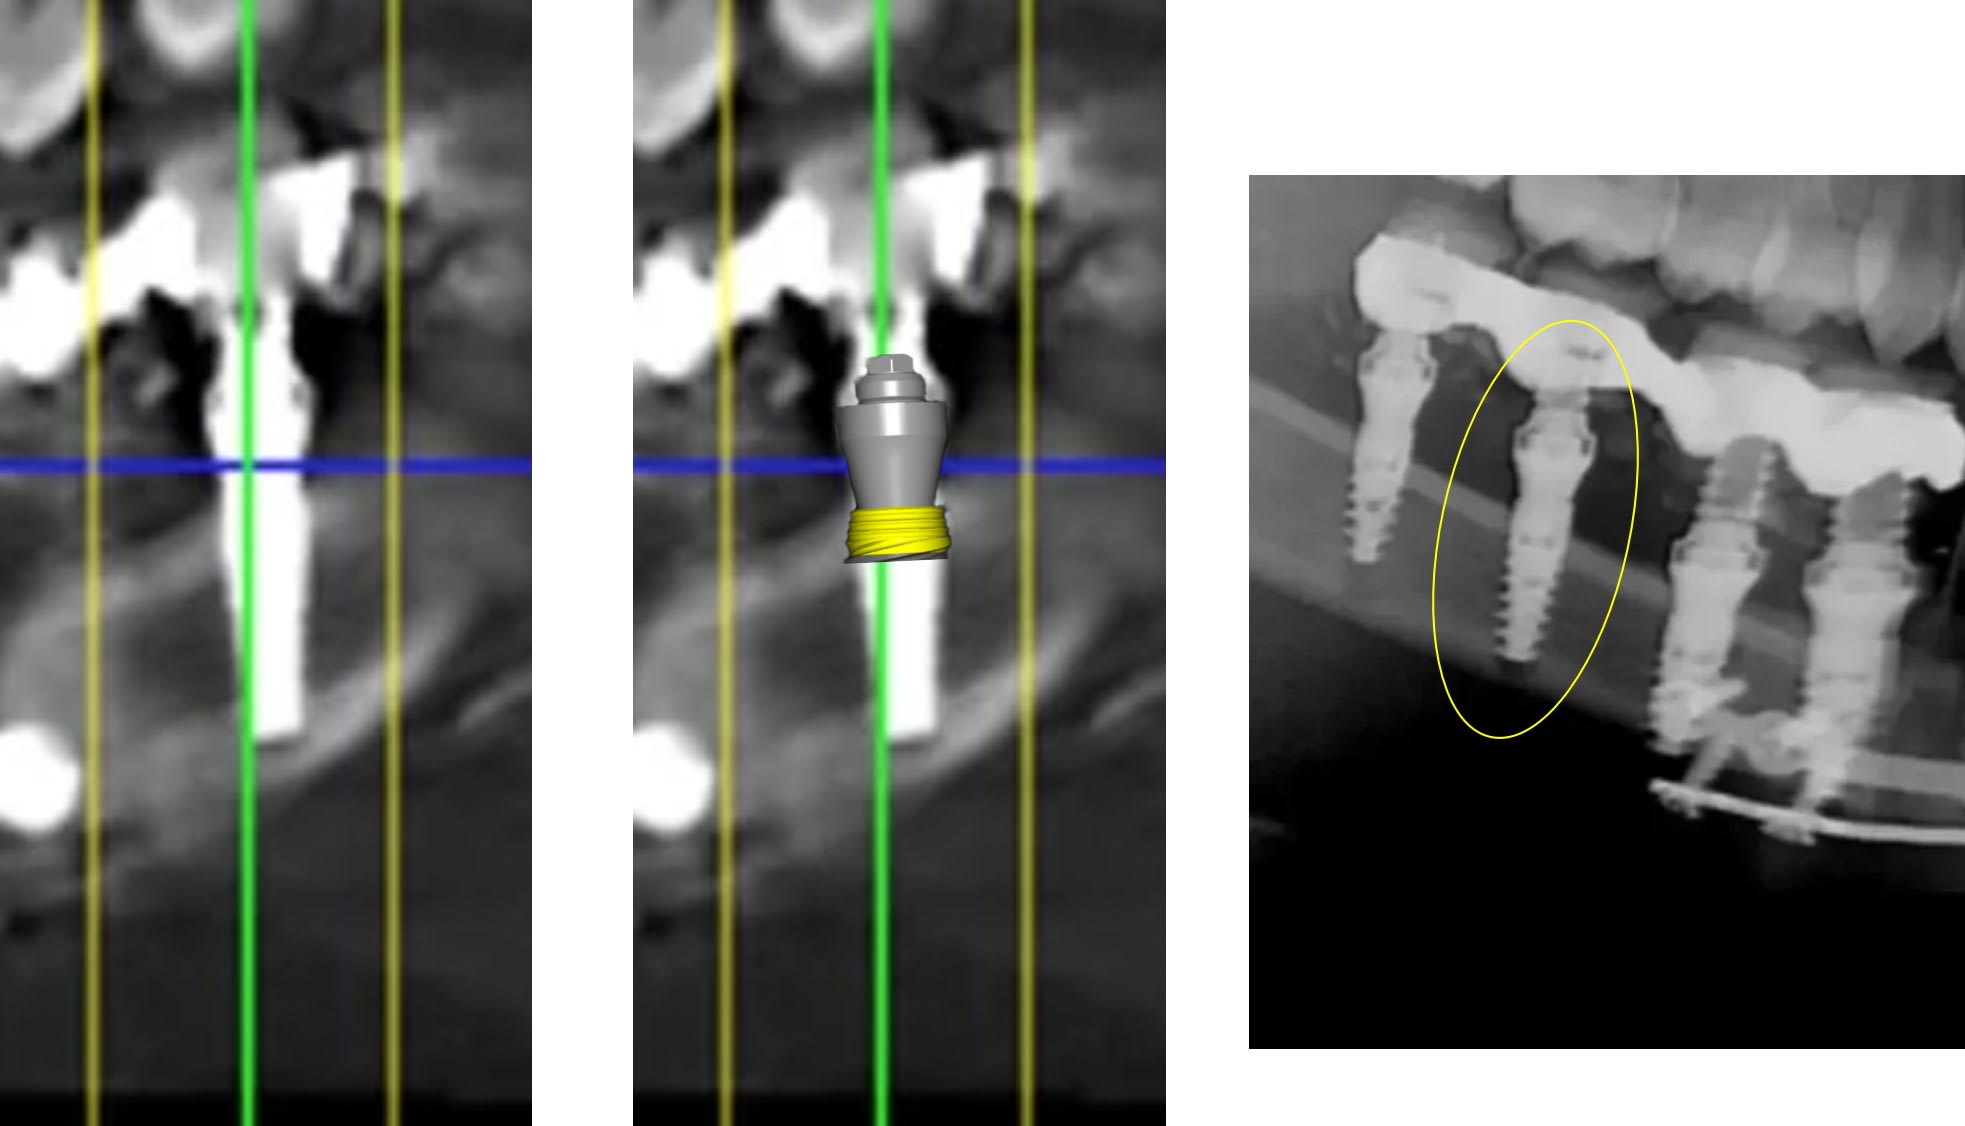

ce qui devrait etre acté c'est que cet implant devrait etre dans l'os... ce qui est tres loin d'etre le cas.

mais bon a part l'implant pas dans l'os : 10/10 :)

> ce qui aurait ete opportun c est d enfuir convenablement ces implants;)

> l implant qui a 5 spires du col a l air a la pose c est ok pour toi ???

> dire que tu presentes ca comme le summum :)))

> vous avez pris des radio per op et vous avez laisse comme ca ?

:))) on reparle de ton implant extra osseux la ???

heureusement que c est ton plus beau cas ;)

Où tu vois 5 spires extra osseuses ?

sur tes radios... apres je pensais en effet que le col de cet implant etait micro fileté... mea culpa... ;)

dans tous les cas l implant c est dans l os ;)

Tu peux être préoccupé par ça où t'intéresser au sujet par exemple une pano nous donne t elle une indication fiable sur la position d'un implant ?